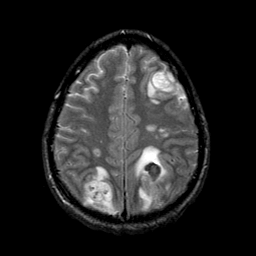

Sarcoma, MR Study #1 mr-t2 -- Slice #18

[Home][Help][Clinical] Slice 18